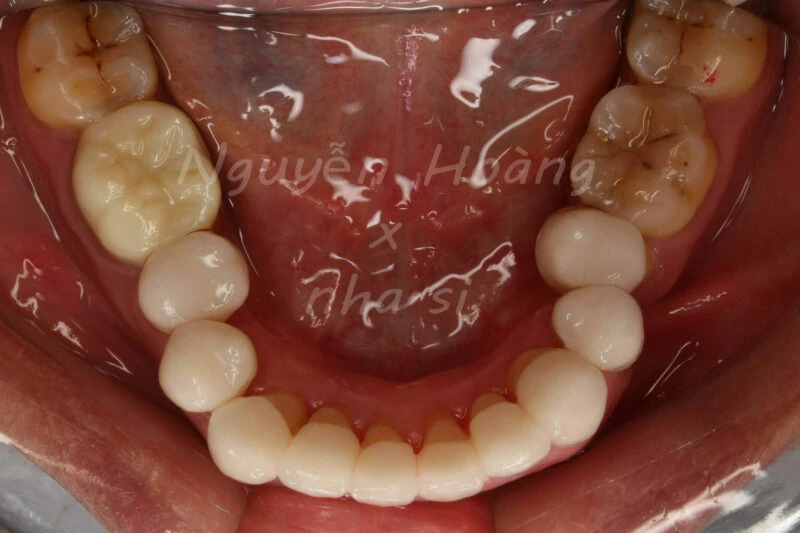

Hình 1: Hàm dưới trước khi phục hình

Đây là tình huống lâm sàng khách hàng muốn làm răng sứ thẩm mỹ cho 20 răng hàm trên và hàm dưới. Mọi chuyện có vẻ đơn giản khi các răng sắp xếp khá đều đặn, khớp cắn không thuộc dạng khó. Tuy nhiên, chỉ có 2 “kẻ phá bĩnh” đó chính là răng 35, 45 có hướng không thuận lợi cho phục hình. Răng 45 nghiêng trong 30 độ, và 35 nghiêng trong 45 độ. Việc này cũng thường gặp trên lâm sàng, khi yêu cầu của khách hàng thì cao (làm đều răng, dựng trục răng, không điều trị tủy) mà tình hình răng miệng thực tế lại không lý tưởng. Vậy bạn chọn làm hay từ chối?